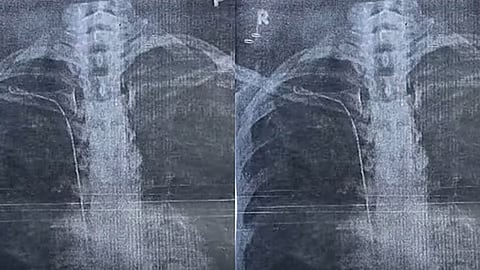

തിരുവനന്തപുരം: ഇരുപത്തിയാറുകാരിയുടെ ജീവിതം വഴിമുട്ടിച്ച് തിരുവനന്തപുരം ജനറൽ ആശുപത്രിയിലെ ഗുരുതര ചികിത്സാ പിഴവ്. തൈറോയ്ഡ് ഗ്രന്ഥി നീക്കം ചെയ്യാനുള്ള ശസ്ത്രക്രിയക്കിടെ 50 സെന്റീ മീറ്റർ നീളമുള്ള സർജിക്കൽ ട്യൂബ് യുവതിയുടെ നെഞ്ചിൽ കുടുങ്ങി. കാട്ടാക്കട സ്വദേശി സുമയ്യയുടെ നെഞ്ചിലാണ് സർജറിക്കിടെ ട്യൂബ് കുടുങ്ങിയിരിക്കുന്നത്.

ഇതുസംബന്ധിച്ച് ജനറൽ ആശുപത്രിയിലെ ഡോക്റ്റർ രാജീവ് കുമാറിനെതിരേ യുവതി പരാതി നൽകിയിട്ടുണ്ട്. 2023 മാർച്ച് 22നാണ് യുവതി സർജറിക്ക് വിധേയയായത്. ആരോഗ്യ പ്രശ്നം ഉണ്ടായപ്പോൾ ഇതേ ഡോക്റ്റർക്ക് കീഴിൽ രണ്ടു വർഷം ചികിത്സ തുടർന്നു. ആരോഗ്യപ്രശ്നം കടുത്തപ്പോൾ മറ്റൊരു ആശുപത്രിയിൽ ചികിത്സ തേടി. എക്സ്റേയിലാണ് നെഞ്ചിനകത്ത് ട്യൂബ് കണ്ടത്.